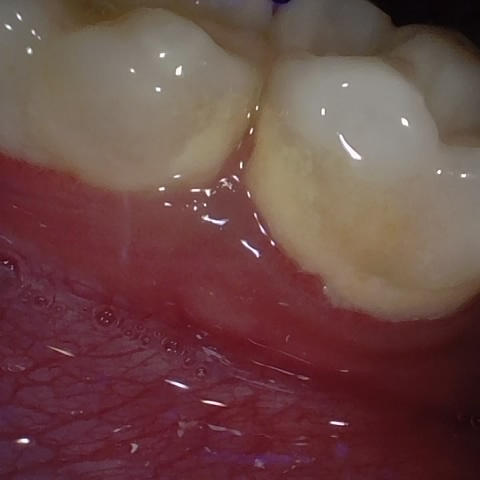

Annotated as "Good"